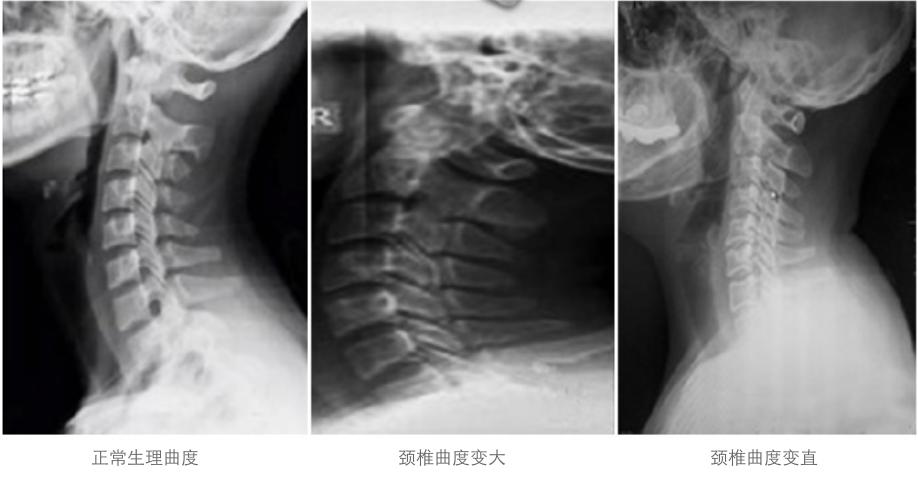

枕头的主要作用,是顺应人体生理弯曲,起到承托头颈,让我们的身体在睡觉的时候也是符合人体的生理弯曲、从而更放松、睡眠质量更好,更健康。

枕头是衬托颈椎到身体最自然的生理曲线状态,而每个人的生理曲线弯曲度都不一样,那么最适合自己的枕头高度也是因人而异的。合适的高度,应该是躺下后,额头和下巴刚好在一条水平线上。